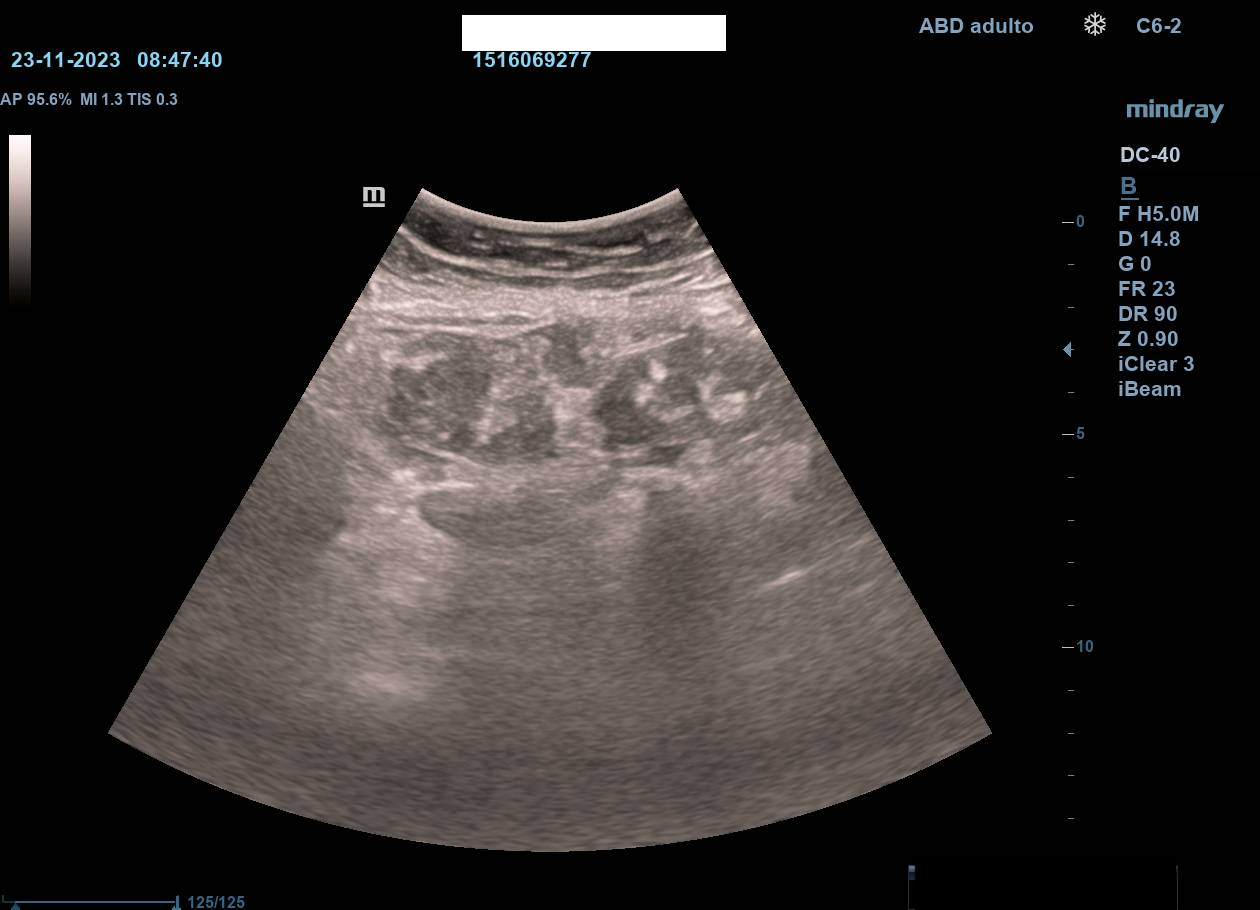

Hallazgos ecográficos

La ecografía en atención primaria permitió un abordaje inicial inmediato, objetivándose dilatación de asas intestinales en la zona de la tumoración, sospecha de ascitis y no visualización de riñón izquierdo (atrofia previa). Estos hallazgos, junto con la exploración, motivaron derivación urgente a Medicina Interna con sospecha de tumoración abdominal.